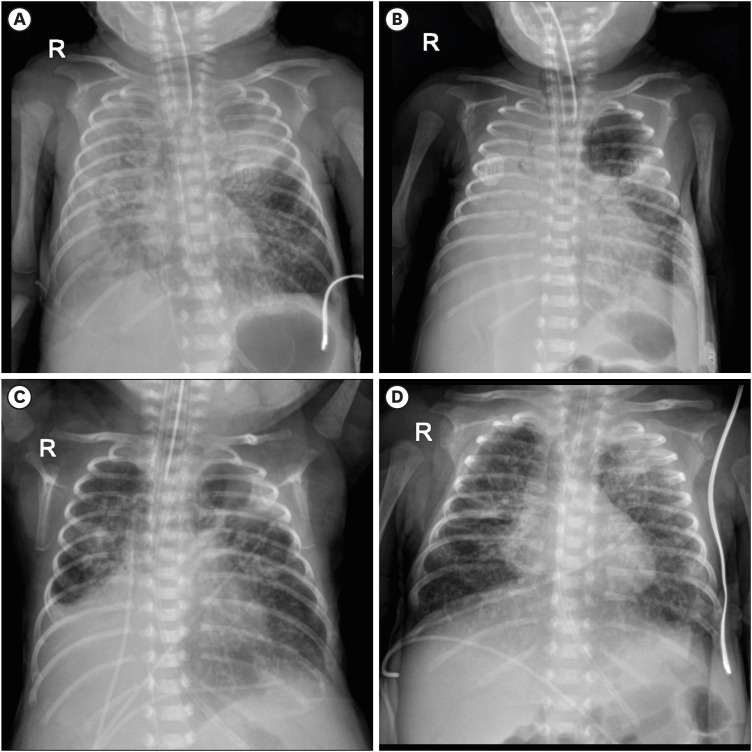

我们报告的情况下,两个极早产儿谁是成功地治疗组织纤溶酶原激活剂(tPA)对危及生命的阻塞性腔内血肿。一名婴儿因胃肠道血肿出现肠穿孔和肠梗阻,而另一名婴儿因气管内血肿出现肺萎陷。分别将tPA直接应用于胃肠道和气管,导致血肿溶解和阻塞缓解。对于治疗方案有限的极早产儿,局部tPA可能是治疗导致胃肠道梗阻或肺萎陷的严重阻塞性腔内血肿的一种有价值的方法。

We report the cases of two extremely preterm infants who were successfully treated with tissue plasminogen activator (tPA) for a life-threatening obstructive intraluminal hematoma. One infant presented with bowel perforation and ileus resulting from a gastrointestinal (GI) hematoma, whereas the other experienced lung collapse due to an intratracheal hematoma. Direct administration of tPA to the GI tract and trachea, respectively, resulted in hematoma lysis and relief of the obstruction. For extremely preterm infants with limited viable treatment options, local tPA may be a valuable approach for managing severe obstructive intraluminal hematomas that lead to GI obstruction or lung collapse.